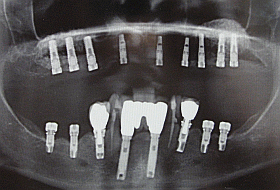

This X-ray shows the final result with All-on-6 (for the upper jaw) & All-on-4 (for the lower jaw) systems where 10 NOBEL BIOCARE – BRANEMARK dental implants were used. This treatment required 6 months healing period between initial placment of implants and fitting of final bridges.

In order to make All-on-6 & All-On-4 restorations successful, some Branemark implants are placed at an angle (see X-ray photo), requiring careful planning and placement of implants, which would in turn provide maximum strength to support final restorations to be screwed onto implants.